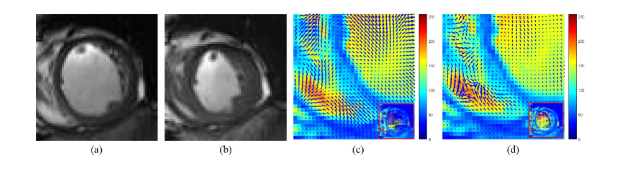

Performance of the optical flow. The purpose of the optical flow is to capture the global motion features. To evaluate the performance of our optical flow algorithm with a deep architecture, we used the average angular error (AAE) to evaluate our deep optical flow and other optical flow approaches. The other optical flow methods, including the Horn and Schunck method, pyramid Horn and Schunck method, intensity-based optical flow method, and phase-based optical flow method, can be found in [12]. The comparison results are shown in Table 3, and visual examples are illustrated in Fig. 4.